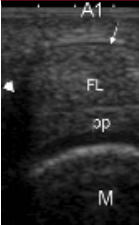

Trigger finger will start as just a little swelling or an inability to fully bend the fingers or fully straighten them. This is because swelling starts to settle in the knuckles of the fingers around the A1 or first pulley in the hand. The knuckles need to be stable and in some cases especially repetitive gripping a person might lose this stability and then become swollen and develop a trigger finger.